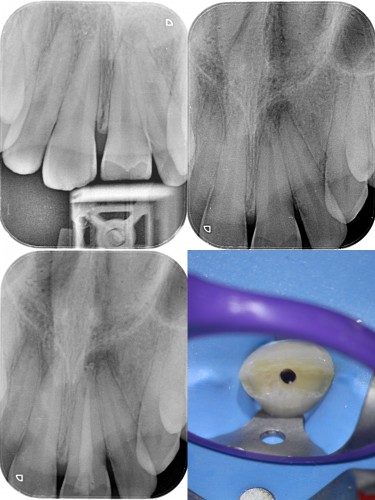

Pt 17yrs male presented with pain and discoloration of #9. After the Access prep,cleaning and shaping , temporary composite restoration was done. After 2 visits of CAOH dressing obutration completed and bleach placed for a week. Composite resoration done in #8 and repeated in #9.